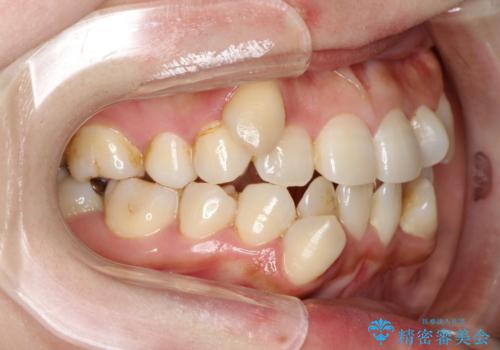

初診時の歯並びの状態としては、上下に強いガタガタがある状態であり、それが原因で口腔内の清掃状態も極めて悪い状況でした。

スペースの不足量が著しく、上下左右の抜歯を伴うワイヤー矯正にて治療を行いました。

また、左上の奥歯に関して親知らずの1つ手前の歯の状態が悪かったため、その歯は抜歯をし親知らずを利用して噛み合わせを作りました。